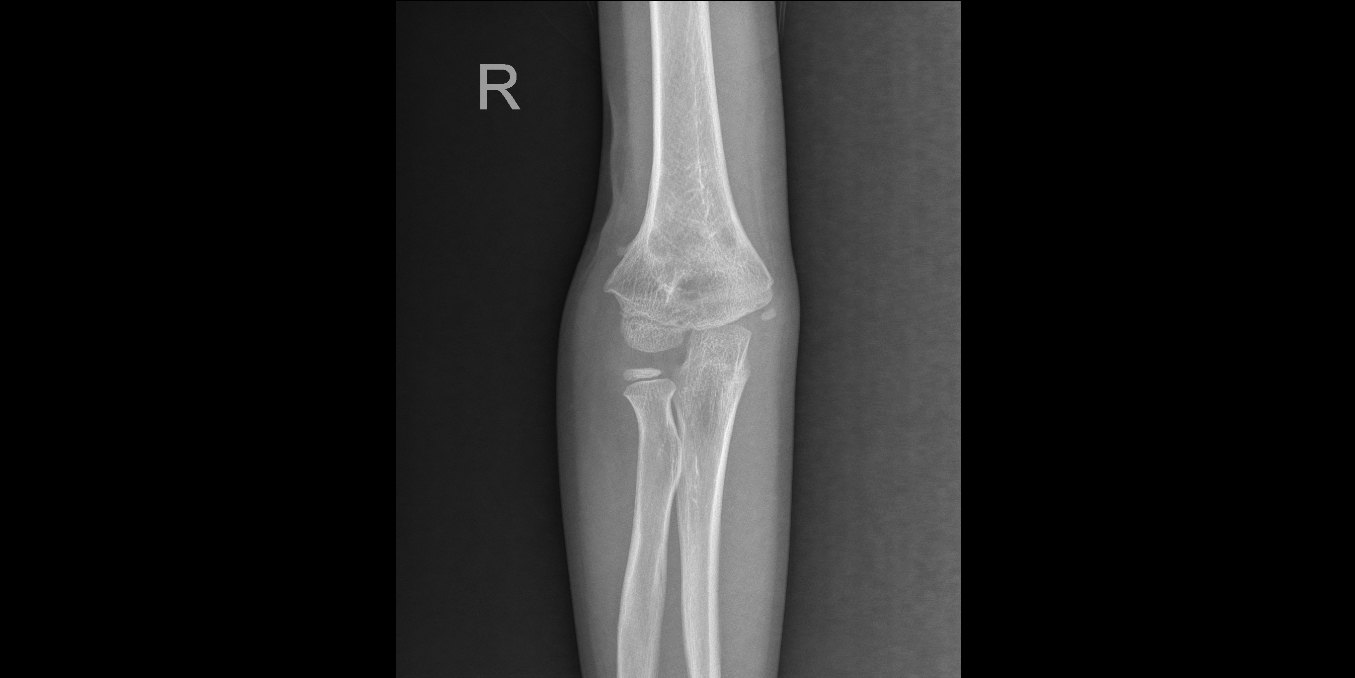

病例分享 | 肘内翻 - 好大夫在线

《丁香创伤系列三》——肘关节创伤篇 [病例帖]